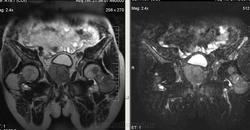

Метастазы рака простаты, кроме измений в позвонках видна сама первичная опухоль и лимфатические узлы (общий и наружный подвздошные слева, ещё один в левой подвздошной ямке).

После добавления томограмм исследования органов малого таза картина стала ещё печальнее...

Да, запустил пациент. До этого были проблемы с мочеиспусканием, рези, болезненность. Лечился самостоятельно от простатита, отмечал временное улучшение.